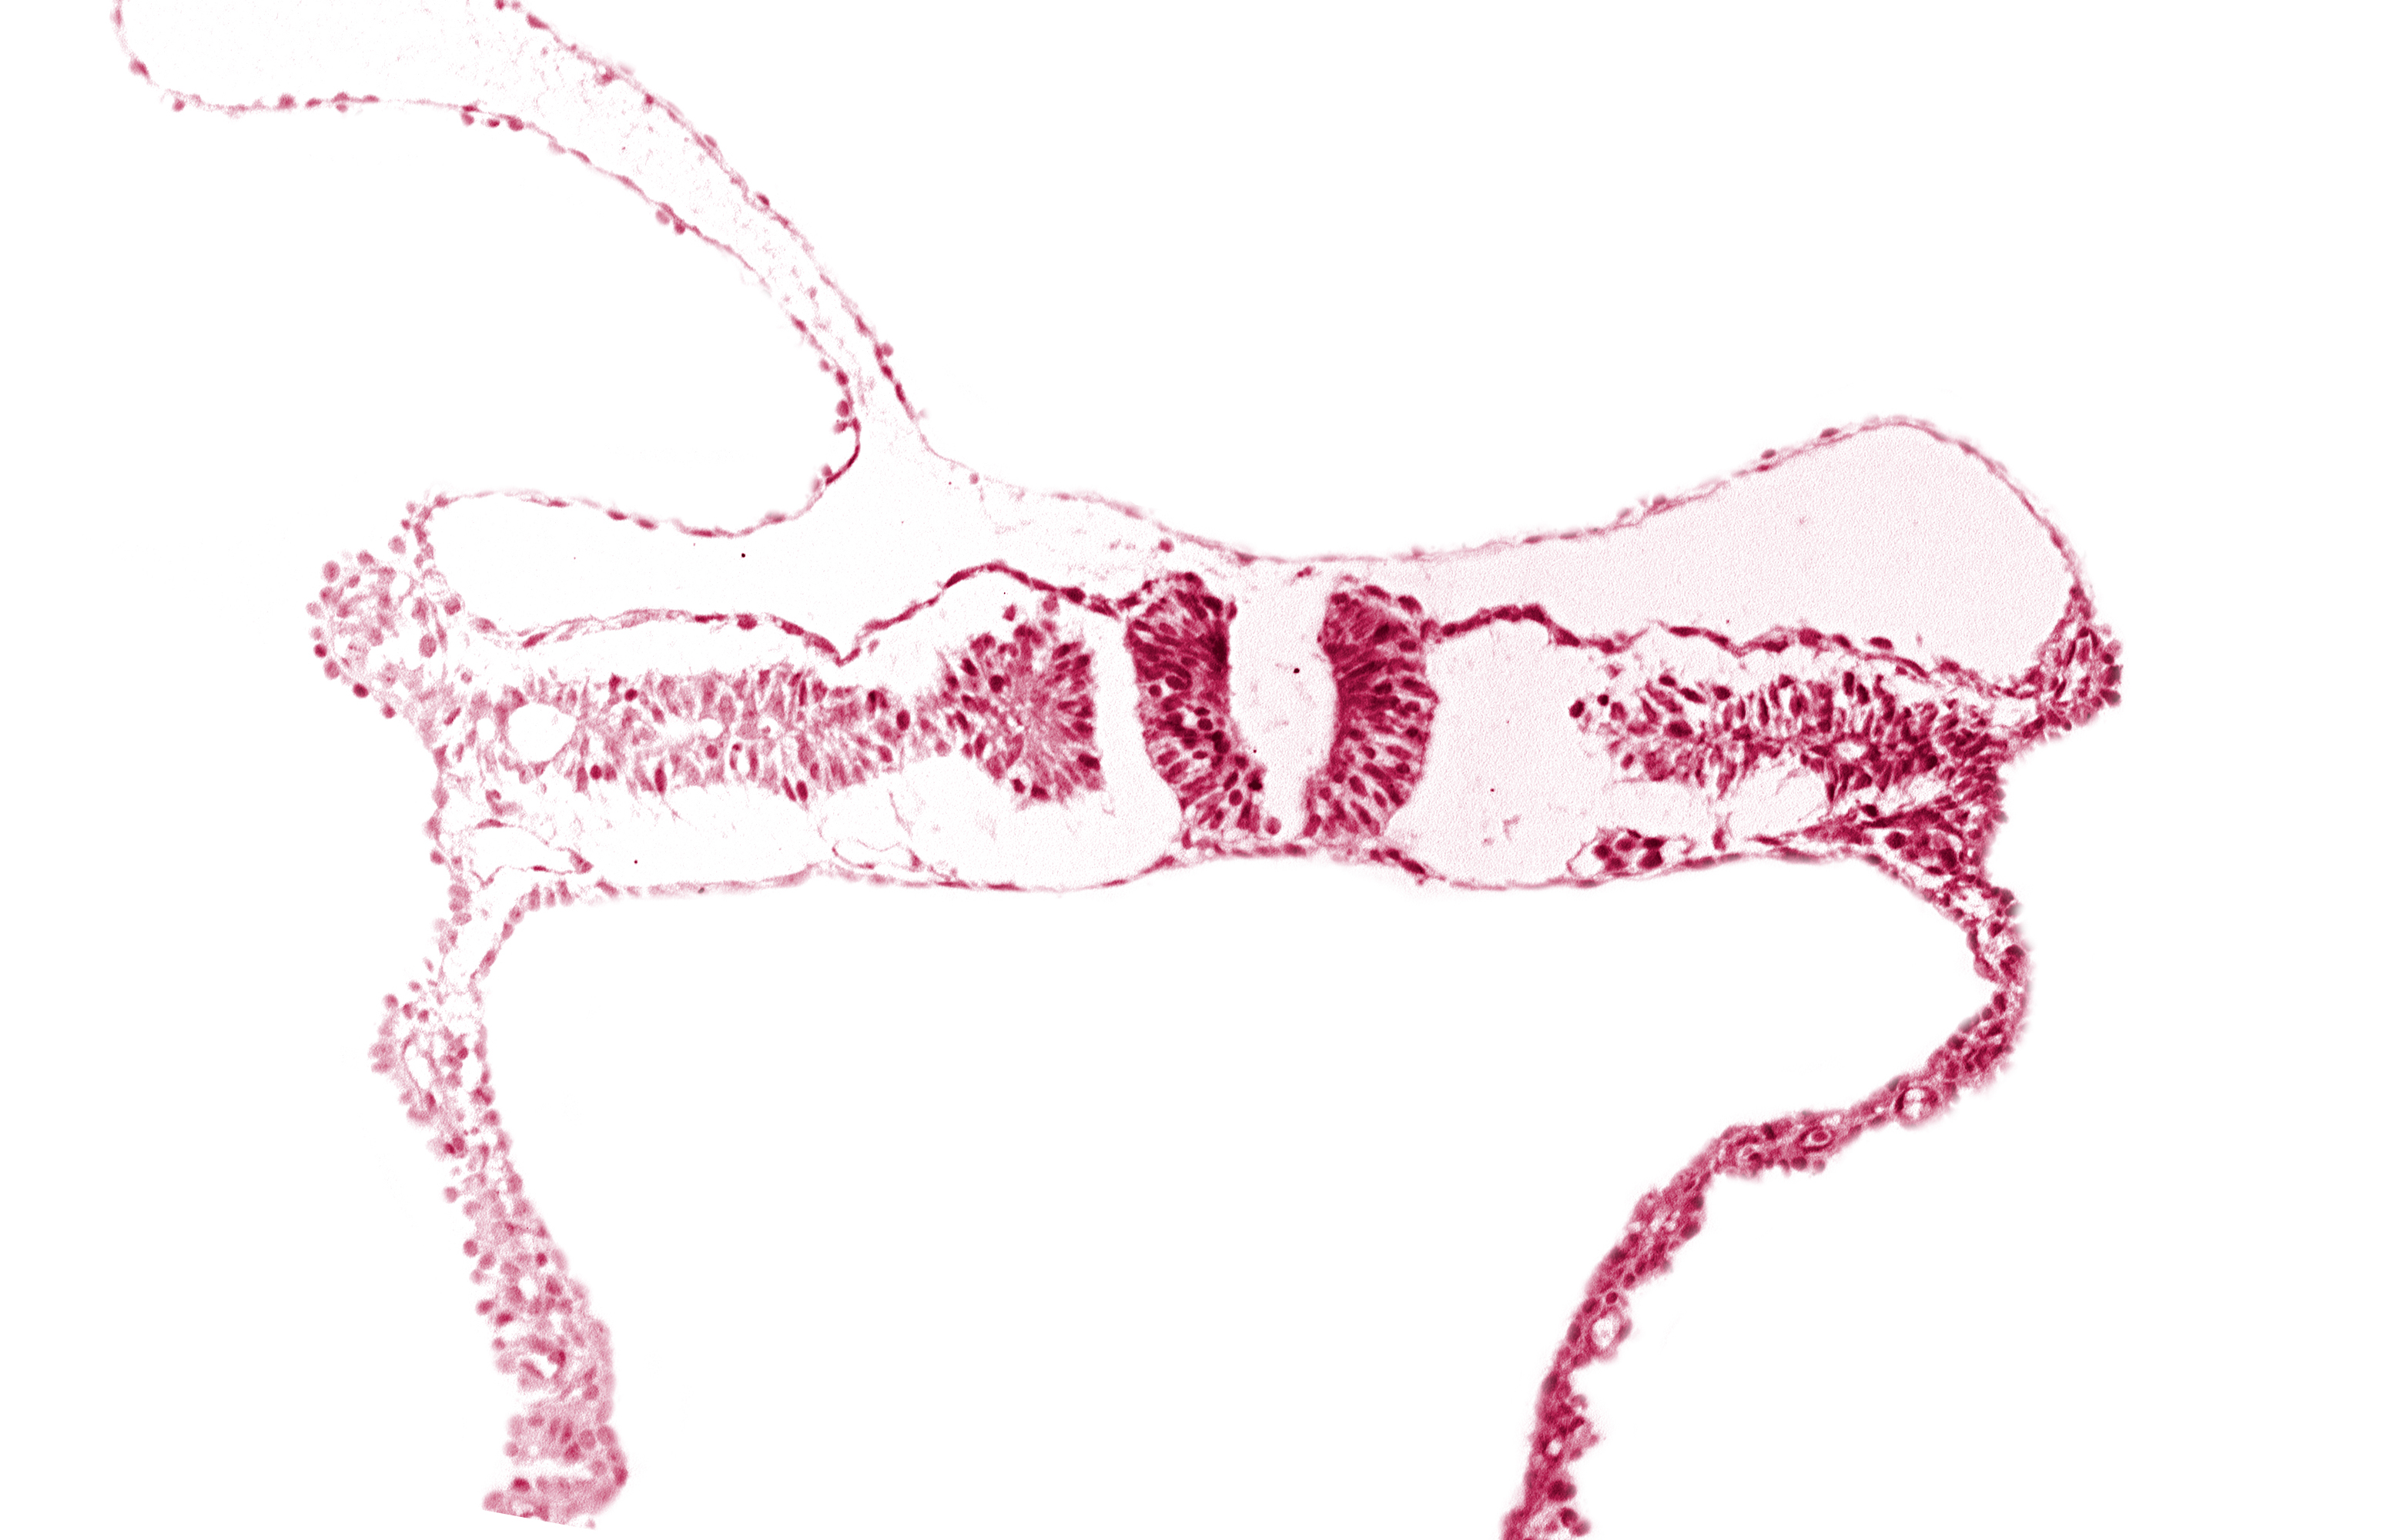

embryonic endoderm, embryonic surface ectoderm, right umbilical vein, somite 6-7 intersegmental region, umbilical vesicle wall endoderm, umbilical vesicle wall mesoderm

Carnegie Embryo #6330   |   Location: 02-09-01

Keywords: embryonic endoderm, embryonic surface ectoderm, right umbilical vein, somite 6-7 intersegmental region, umbilical vesicle wall endoderm, umbilical vesicle wall mesoderm